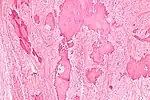

| Low magnification micrograph of a calcified ovarian fibroma in the context of nevoid basal cell carcinoma syndrome. H&E stain. | |

On gross pathology, they are firm and white or tan. On microscopic examination, there are intersecting bundles of spindle cells producing collagen.

There may be thecomatous areas (fibrothecoma). The presence of an ovarian fibroma can cause ovarian torsion in some cases.

Diagnosis is usually made by ultrasonography showing a solid ovarian lesion, or, on some occasions, mixed tumors with solid and cystic components.[1] Computed tomography and magnetic resonance imaging can also be used to diagnose fibromas. In a series of 16 patients, 5 (28%) showed elevated levels of CA-125.[1] Histopathology demonstrates spindle-shaped fibroblastic cells and abundant collagen.[3]

Variants with edema can be associated with Meigs' syndrome. They may be a part of nevoid basal cell carcinoma syndrome (Gorlin syndrome).[4]